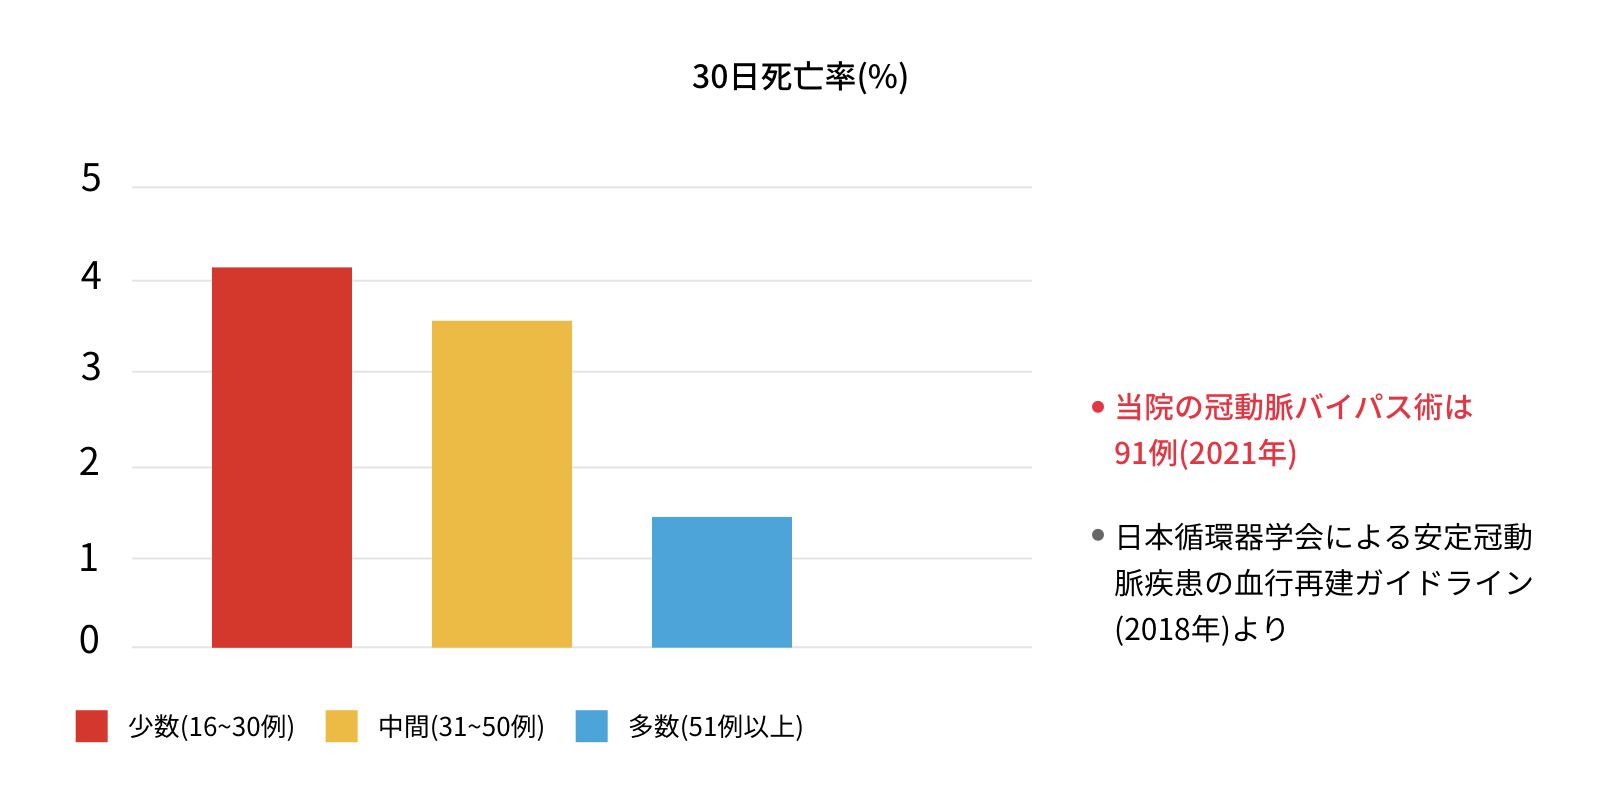

冠動脈バイパス術は、施設間で治療成績に差があると言われています。術後30日以内の死亡率は,年間の施設の手術件数で分けられます。年間手術件数が多い施設が安全に手術を行っている事になります。当院では、開院(1999年)より1500例を超える冠動脈バイパス術を行ってまいりました。